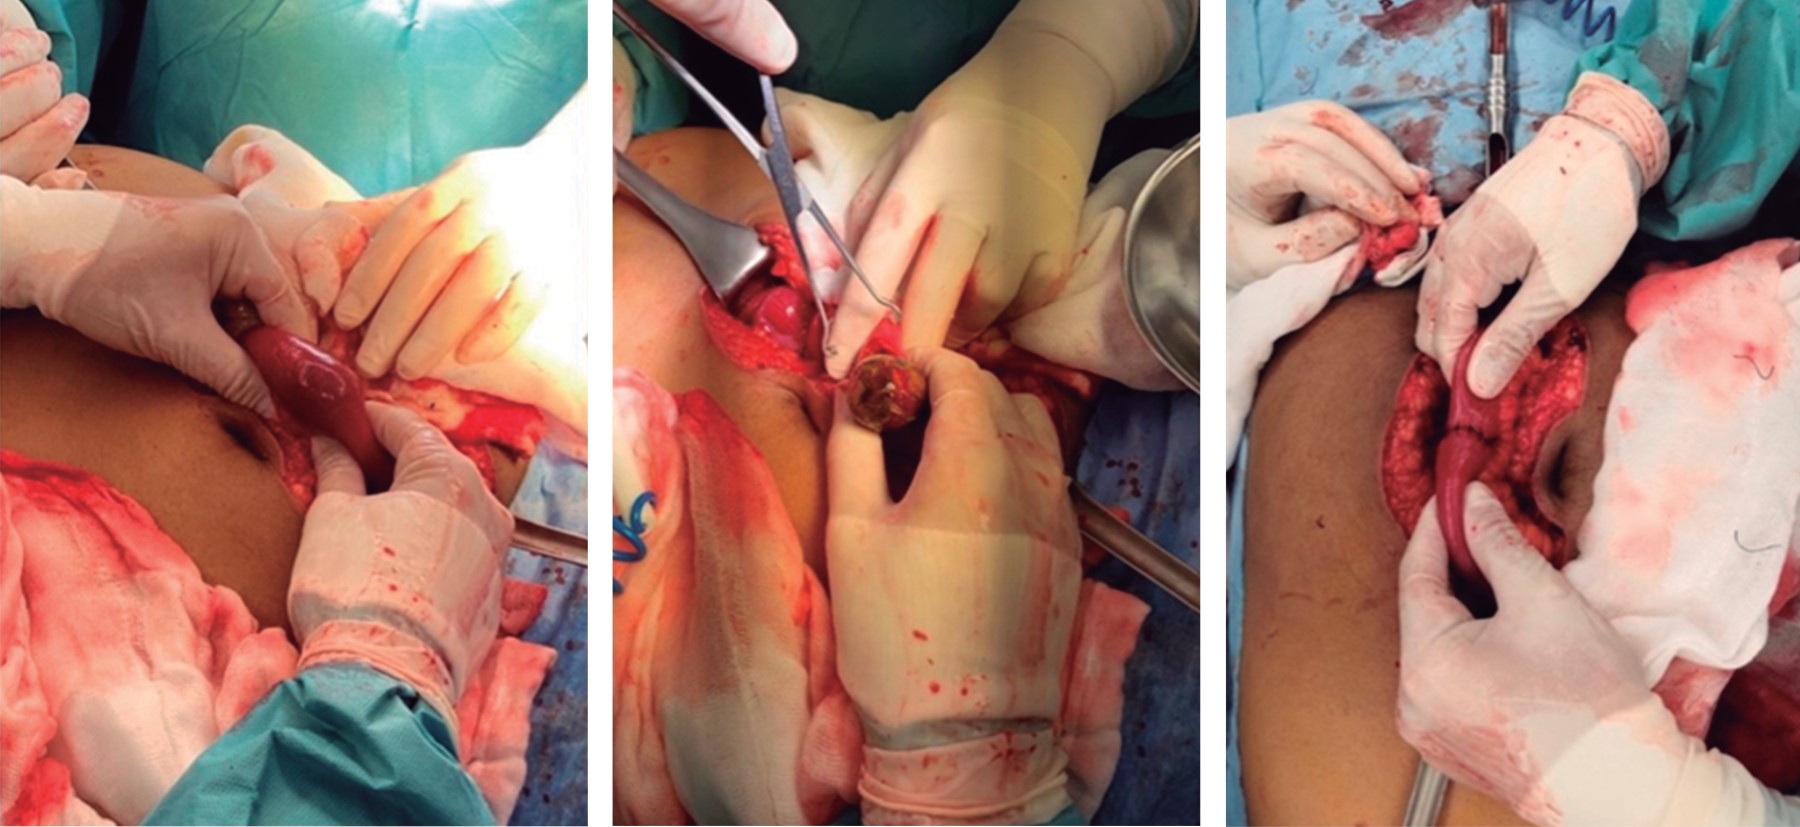

Radiografías de abdomen de pie y decúbito (Figura 1): se evidenció imagen en pila de monedas, así como distensión de asas del intestino delgado, con ausencia de gas en intestino distal.

En cuanto a los estudios de imagen se inició con las radiografías de abdomen en la cual se esperaba evidenciar la triada de Rigler: cálculo biliar ectópico, neumobilia y distensión de asas intestinales; se considera el diagnóstico cuando están presentes dos de éstos, y se habla de la tétrada de Rigler cuando se documenta el cambio de posición del cálculo con respecto a la radiografía previa.1,2 En nuestro paciente no fue posible encontrar estos hallazgos, ya que en la radiografía de abdomen únicamente se evidenció nivel hidroaéreo en hemiabdomen derecho y distensión de asas intestinales, así como ausencia de aire en intestino distal.

Chang y colegas, en 2018, reportaron que la triada de Rigler en las radiografías se encuentra presente en 14 a 53% de los casos, cuya sensibilidad es de 40 a 70%; así como la visualización de los cálculos biliares en 10 a 20% de los casos, aquellos que contienen calcio para ser radioopacos.2,6 Esto también fue congruente con lo encontrado en nuestro paciente, razón por la que, se pensó en un cálculo de colesterol y, al no contar con una causa franca de la obstrucción, se solicitó tomografía de abdomen simple y contrastada, la cual actualmente se considera el estudio de elección para el diagnóstico, pues en ella es posible visualizar hasta en 80% de los casos la triada de Rigler con aproximadamente 90% de sensibilidad.1,6

Figura 1